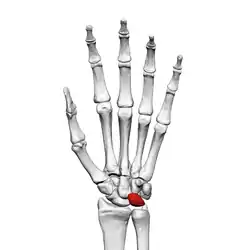

Lunate bone of the left hand (shown in red). Animation.

The lunate bone (semilunar bone) is a carpal bone in the human hand. It is distinguished by its deep concavity and crescentic outline. It is situated in the center of the proximal row carpal bones, which lie between the ulna and radius and the hand. The lunate carpal bone is situated between the lateral scaphoid bone and medial triquetral bone.

The lunate is a crescent-shaped carpal bone found within the hand. The lunate is found within the proximal row of carpal bones. Proximally, it abuts the radius. Laterally, it articulates with the scaphoid bone, medially with the triquetral bone, and distally with the capitate bone. The lunate also articulates on its distal and medial surface with the hamate bone.[2]: 708 [3]